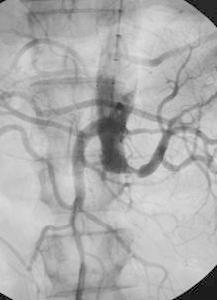

腎動脈造影腎動脈部分閉塞無腎功能明顯變化時,很少診斷為血栓栓塞性腎臟疾病,因為其他病因更常見。嚴重創傷後的急性腎衰的鑑別診斷包括橫紋肌溶解,膿毒症和長時間低血壓。主動脈瘤或嚴重動脈粥樣硬化的病人中,較急性腎動脈血栓形成更多的是動脈粥樣栓塞性腎臟損害。因為這些情況治療不同,迅速診斷(最有效的是通過腎臟影像)是必要的,以保護儘可能多的腎實質。

1支或2支腎動脈慢性閉塞可導致腎血管性高血壓。如發現血漿腎素水平增高,特別在套用卡托普利以後提示該診斷的可能性。靜脈腎盂造影病側腎臟較小,造影劑排空延遲;放射性腎圖亦示兩側腎灌注和功能不同。腎動脈造影對確定閉塞的解剖位置是重要的。分側測定腎靜脈腎素水平可提示來自缺血腎的靜脈血中腎素活性增高。